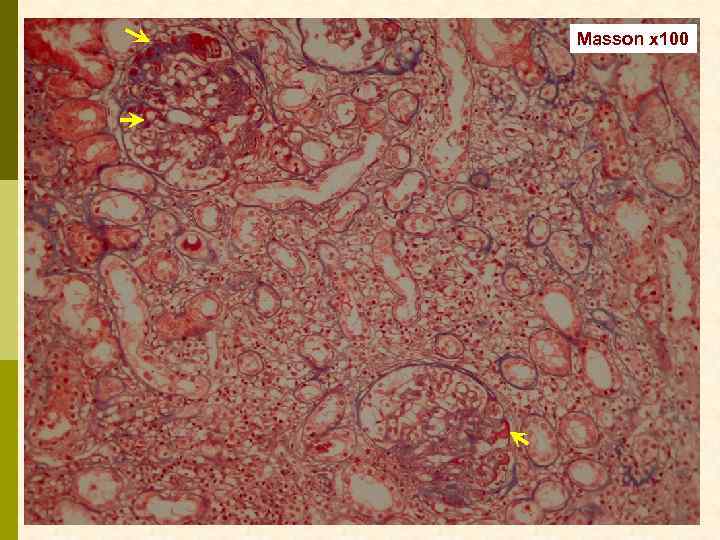

Б. Клинический случай № 21631 Александр К. , 1972 г. рожд. В 1999 г. выявлен гепатит С, в 2003 г. – ВИЧ. С июня 2006 г. – отеки, быстрое развитие анасарки. Почки по УЗИ 13 7 см. Протеинурия 9, 6 г/сут, креатинин 0, 19 мм/л, холестерин 18 мм/л. Обнаружен Ig. M-криоглобулин. 02. 11. 2006 - диагностическая нефробиопсия.

PAS x 100

Masson x 100

Masson x 100

Jones x 100

Jones x 100

PAS x 400

PAS x 400

Jones x 400

Jones x 400

Masson x 400

Masson x 400

Masson x 400

Иммунофлюоресцентное исследование: p Клубочки: Ig. G (2+), Ig. M (3+), C 3 (2+), kappa (3+), lambda (1 -2+) - диффузная, субэндотелиальная и интракапиллярная, крупно-гранулярная экспрессия; p Стенки артериол: C 3 (2+); p Цилиндры: Ig. G (2+), Ig. A (3+), Ig. M (2+), C 3 (3+), kappa (3+), lambda (2+); p Реабсорбированные белковые капли: kappa (3+).

Предварительное гистологическое заключение: p Мембрано-пролиферативный, HCV-ассоциированный, криоглобулинемический(? ) гломерулонефрит с полным склерозом 47% клубочков, сегментарным склерозом 22% клубочков и формированием полулуний в 15% клубочков; p диффузно-очаговый выраженный острый канальцевый некроз; p выраженный артерио-артериолосклероз. Примечание: Криоглобулинемическая природа поражения будет уточняться при ЭМ-исследовании.

Заключение p Мембрано-пролиферативный гломерулонефрит, криоглобулинемический, ВИЧ-ассоциированный, на фоне гепатита С